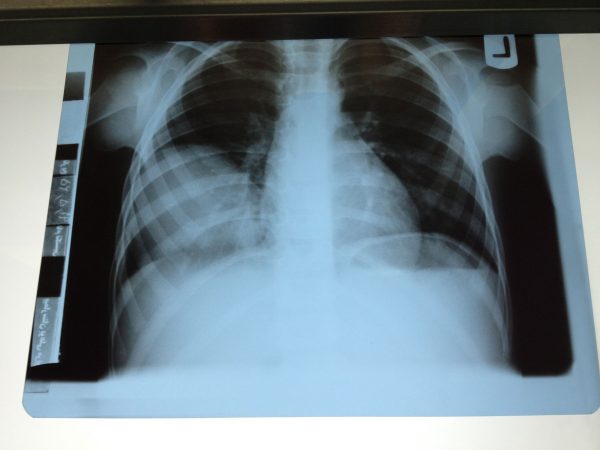

خروج میخ از سینه بیمار 47 ساله

پس از آزادسازی بافت ریه، بدون عمل جراحی قلب باز و فقط با دو برش یک سانتیمتری به آرامی پرده پریکارد آزاد شد و جسم خارجی بیرون آورده شده و سپس پریکارد ترمیم شد. بیمار 24 ساعت بعد با حال عمومی خوب از بیمارستان مرخص شد.